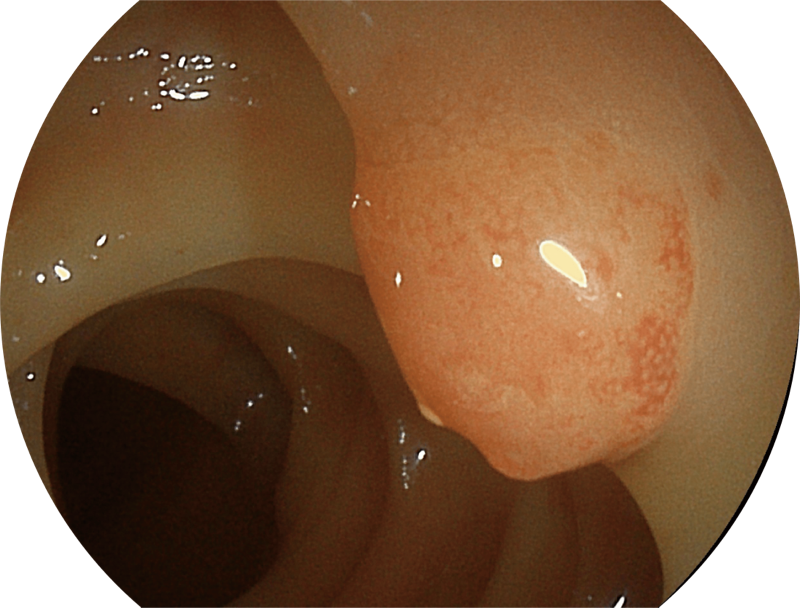

百万级像素高清传感器,1080P全高清视频信号输出,图像清晰。

能够凸显黏膜浅层血管轮廓和黏膜表面微结构,适用于中、近景观察下的早癌精确诊断。

在临床操作中,时刻保持黏膜清洁和视野清晰,更快寻找出血点,满足临床治疗。